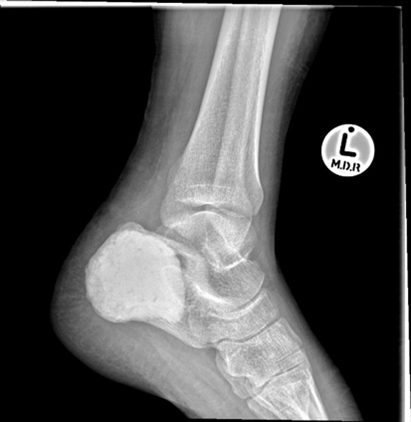

Curretage and bone grafting. The above images show an aneurysmal bone cyst of the left calcaneus. This is represented by a lytic process that looks soap bubbly on the initial X-rays. Because the patient is young and it is a benign lesion, a curettage and bone grafting has been performed. The series of X-rays following the bone grafting show the body’s incorporation of the graft, replacing it with the patient’s own bone.